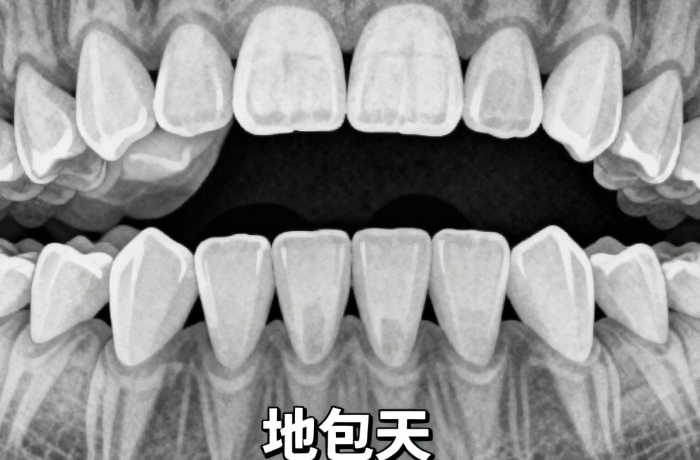

簡單的牙齒排齊與涉及拔牙、骨釘(支抗釘)、頜骨調(diào)整的復(fù)雜病例,治療計(jì)劃和所需技術(shù)完全不同。例如,如果需要拔除4顆前磨牙來提供空間,拔牙費(fèi)用(每顆約150-600元)和額外的矯正設(shè)計(jì)費(fèi)就會增加總成本。

區(qū)別主要在矯治器的定制化程度和干預(yù)的穩(wěn)準(zhǔn)性。6800元起的MRC屬于功能性矯治器,更側(cè)重于肌肉訓(xùn)練和習(xí)慣糾正。而2萬元起的羅慕等矯治器,是根據(jù)孩子牙齒模型預(yù)成的,對牙齒的三維移動控制更精細(xì)。選擇哪種,需由醫(yī)生評估孩子具體的錯頜類型后決定。